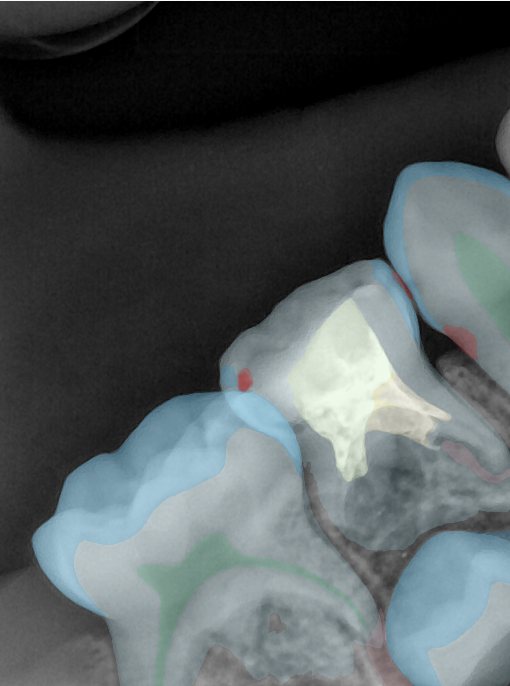

CR/DR 牙齿分割阶段记录

当前进展

- 完成了 CR/DR 牙齿相关分割训练

- 当前结果已经达到阶段预期,但仍有细节问题需要继续处理

相关测试

遇到的问题

- 训练过程中出现过 mask 下移问题

- 部分结果会出现 box 填充异常

- mask 边缘仍然有比较明显的锯齿感

参考

第二版算法问题测试

结论:修复类出现了不鲁棒的情况,后续需要加入轮廓的扩充数据进行增强。